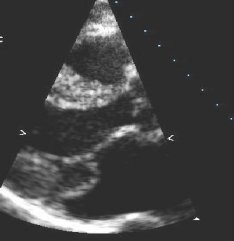

Mitral regurgitation

Parasternal long-axis view showing posterior mitral leaflet prolapse

From the collection of Samir Kapadia and Mehdi H. Shishehbor